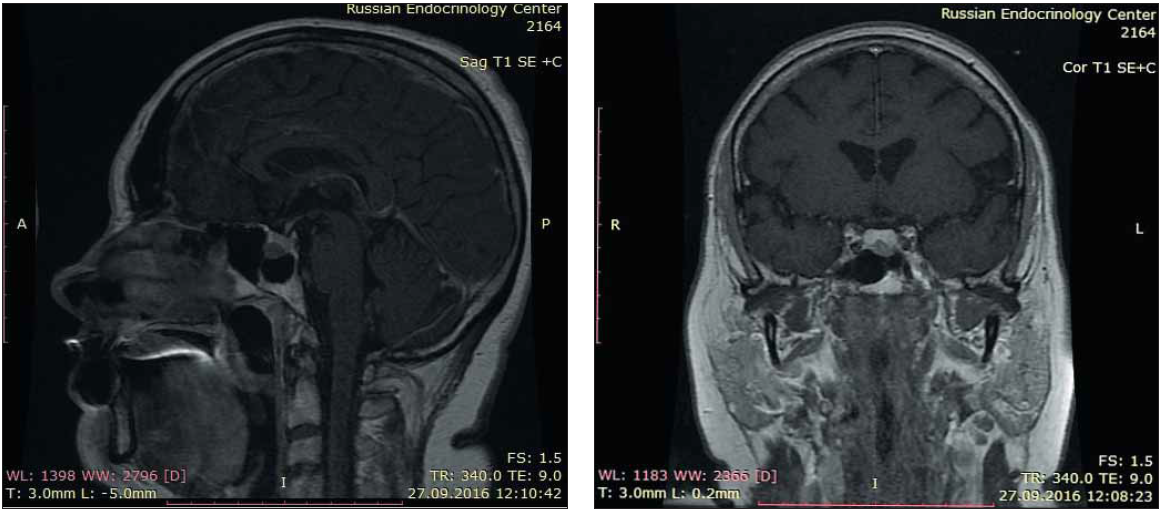

4. Рис. 4. Данные МР-исследования головного мозга через 6 месяцев после оперативного лечения.

Subject

Type Исследовательские инструменты

View (705KB)

Indexing metadata ▾